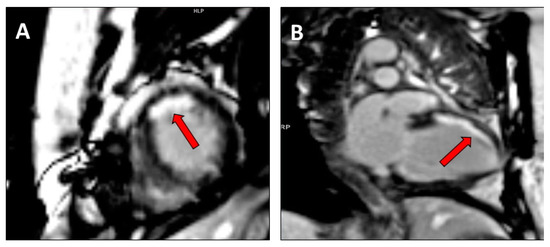

2.2. Assessment of Myocardial Contractile Reserve and Scar Burden

- Bilchick, K.C.; Dimaano, V.; Wu, K.C.; Helm, R.H.; Weiss, R.G.; Lima, J.A.; Berger, R.D.; Tomaselli, G.F.; Bluemke, D.A.; Halperin, H.R.; et al. Cardiac magnetic resonance assessment of dyssynchrony and myocardial scar predicts function class improvement following cardiac resynchronization therapy. JACC Cardiovasc. Imaging 2008, 1, 561–568. [Google Scholar] [CrossRef] [PubMed]

- Aalen, J.M.; Donal, E.; Larsen, C.K.; Duchenne, J.; Lederlin, M.; Cvijic, M.; Hubert, A.; Voros, G.; Leclercq, C.; Bogaert, J.; et al. Imaging predictors of response to cardiac resynchronization therapy: Left ventricular work asymmetry by echocardiography and septal viability by cardiac magnetic resonance. Eur. Heart J. 2020, in press. [Google Scholar] [CrossRef] [PubMed]

- Leyva, F.; Foley, P.W.; Chalil, S.; Ratib, K.; Smith, R.E.; Prinzen, F.; Auricchio, A. Cardiac resynchronization therapy guided by late gadolinium-enhancement cardiovascular magnetic resonance. J. Cardiovasc. Magn. Reson. 2011, 13, 29. [Google Scholar] [CrossRef]

- Taylor, R.J.; Umar, F.; Panting, J.R.; Stegemann, B.; Leyva, F. Left ventricular lead position, mechanical activation, and myocardial scar in relation to left ventricular reverse remodeling and clinical outcomes after cardiac resynchronization therapy: A feature-tracking and contrast-enhanced cardiovascular magnetic resonance study. Heart Rhythm. 2016, 13, 481–489. [Google Scholar] [PubMed]